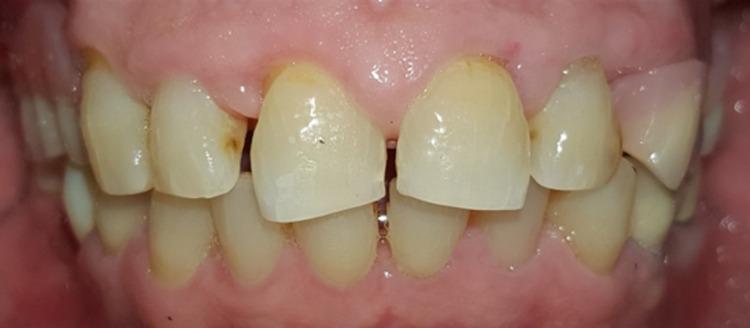

Gingival enlargement may manifest as a side effect of medications (calcium channel blockers, anticonvulsants, or immunosuppressants) and may be associated with inflammation, malignancy, or genetic inheritance. This condition has a significant impact on a patient's quality of life and affects their oral health status. This case report describes the management of a 68-year-old gentleman who presented with generalized gingival enlargement and chronic periapical abscess originating from tooth 34, which served as an abutment for a fixed partial prosthesis. The patient's medical history revealed that felodipine, an antihypertensive medication, was prescribed to him. A comprehensive treatment plan was developed to improve the patient's quality of life.

牙龈增生可能表现为药物(钙通道阻滞剂、抗惊厥药或免疫抑制剂)的副作用,也可能与炎症、恶性肿瘤或遗传因素有关。这种情况对患者的生活质量有重大影响,并会影响他们的口腔健康状况。本病例报告描述了一位68岁男性患者的治疗过程,该患者出现了广泛性牙龈增生以及源自34号牙的慢性根尖周脓肿,34号牙是固定局部义齿的基牙。患者的病史显示,他正在服用降压药非洛地平。制定了一个全面的治疗计划以改善患者的生活质量。